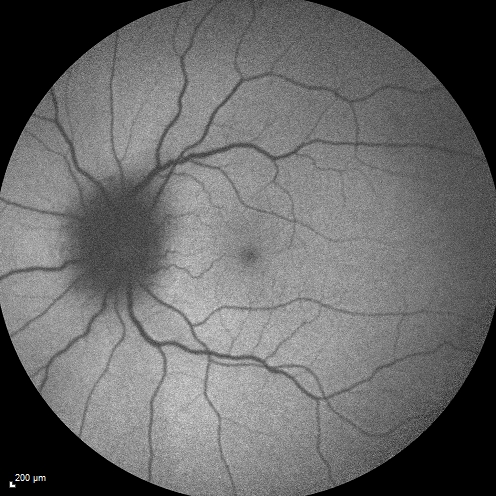

Syphillitic Optic Neuropathy and Maculopathy

46 year old woman with 2 weeks of vision loss OD.  VA 20/200 OD; 20/20 OS.  there are posterior vitreous cells on OCT in both eyes.  ICG, FAF, and FA show an abnormal macula OD.  VA improved to 20/30 within a month with treatment with PCN.